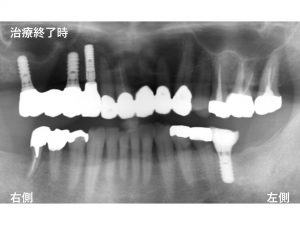

以下が治療後です。

上顎右側を4歯欠損として考え、3本のインプラントで4歯分の被せ物を作成する

インプラントブリッジとしました。